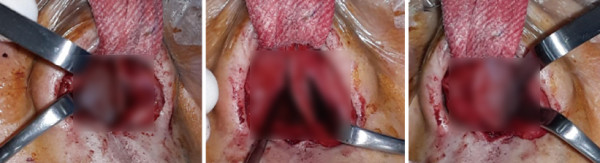

수술 전 CT. 비중격 만곡이 보였다. 골부와 연골부의 좌측 만곡과 spur가 관찰되며 전체적으로

C-shape deviation이 확인되었다. 비중격 만곡으로 인해 측면에서 비중격의 음영 소실도 보였다.

Cottle test에서는 좌측에서 positive가 관찰되 었으며, 흡기 시 우측 비익연골의 허탈이 관찰되었다. 내원 당시 시행한 CT상 비중격의 골부와 연골부 상단에서 좌측으로 만곡된 C-shape deviation이 확인되었다.